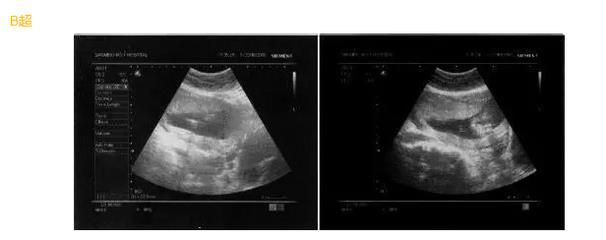

B超采用的是超声诊断技术,通过一个超声探头发射超声波,使超声波遇到屏障传回声波,我们可以利用电脑收集这些声波,转换成二维图像在屏幕上显示出来。但是B超通过超声探头测得的图像是黑白的,只能观测到胎儿的组织结构,测量胎儿的大概尺寸。